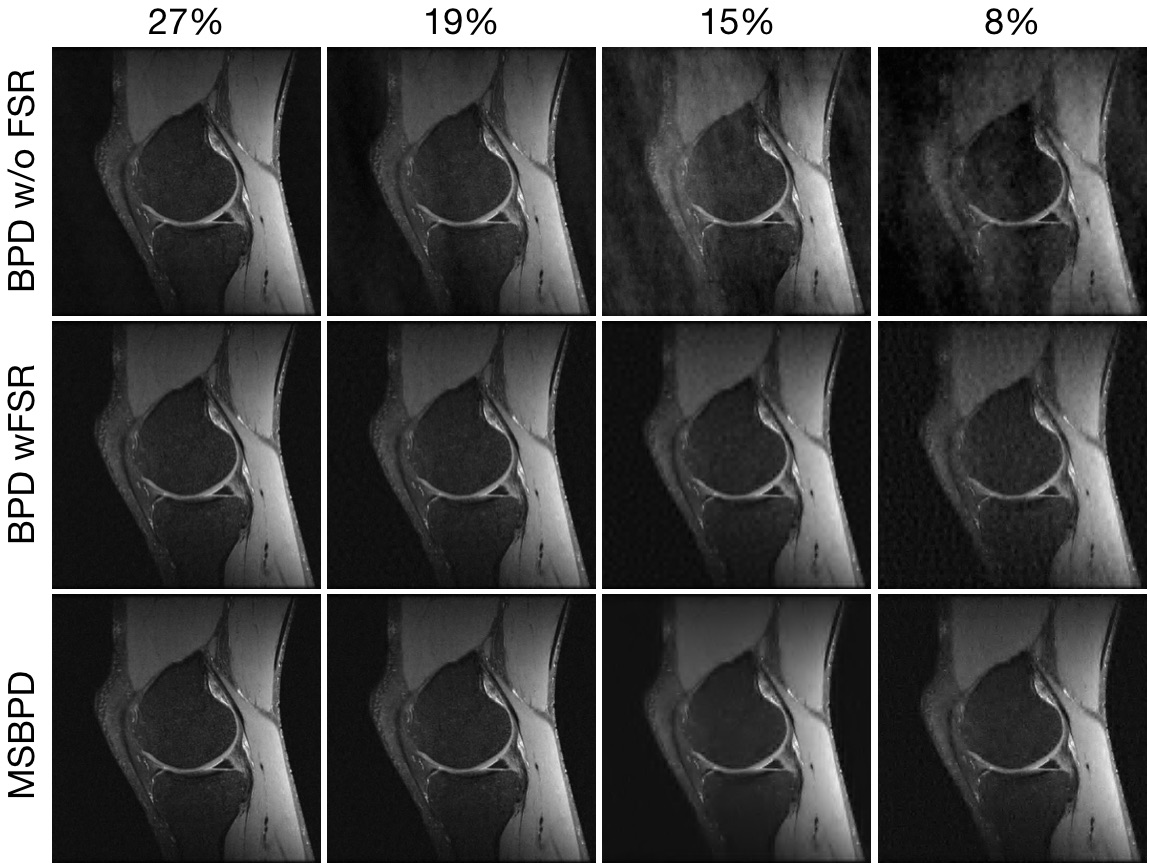

Figure 5 shows reconstructions using BPD and MSBPD. As can be observed in Fig. 5, MSBPD offers the highest quality reconstruction for all sampling percentages. The improvements become more noticeable as the sampling percentage is reduced.

Refer to caption

Figure 5: Reconstructions of MR images of the the knee with different sampling percentages without and with the Fully Sampled Region (FSR).

Table 1 shows the relative errors for the reconstructions in Fig. 5. In all cases, MSBPD yields the lowest relative error. The most significant improvement comes by including the FSR in the samples; a minor gain is attained by using MSBPD over BPD on this sampling pattern. The improvement is more pronounced as the sampling percentage decreases.

In Fig. 6, we zoom into the reconstruction of the knee from 8% of data. This figure shows fewer wavelet artifacts in the result of MSBPD than exist in the result of BPD with either sampling pattern.